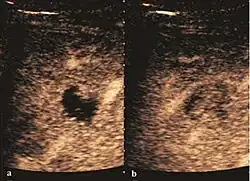

Hydatid liver cyst. Diagnostic criteria are the presence of membranes and sediment inside.

The ultrasound appearance is a well defined lesion, with very thin, almost unapparent walls, without circulatory signal at Doppler or CEUS investigation. The content is transonic suggesting fluid composition. The presence of membranes, abundant sediment or cysts inside is suggestive for parasitic, hydatid nature. Posterior from the lesion the acoustic enhancement phenomenon is seen, which strengthens the suspicion of fluid mass. They typically displace normal liver vessels but no vascular or biliary invasion occurs.

They can be single or multiple, with variable size, generally less than 20 mm (congenital). Rarely, sizes can reach several centimeters, leading up to the substitution of a whole liver lobe (acquired, parasitic). They may be associated with renal cysts; in this case the disease has a hereditary, autosomal dominant transmission (von Hippel Lindau disease).